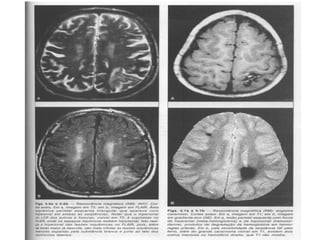

O AVE isquemico é o mais comum e corresponde 61 a 81% dos

AVEs; enquanto o AVE hemorrágico corresponde de 12 a 24%.

(Sullivan, 2004)

ETIOLOGIA O AVE isquemicoé o mais comum e corresponde 61 a 81% dos AVEs; enquanto o AVE hemorrágico corresponde de 12 a 24%. (Sullivan, 2004)